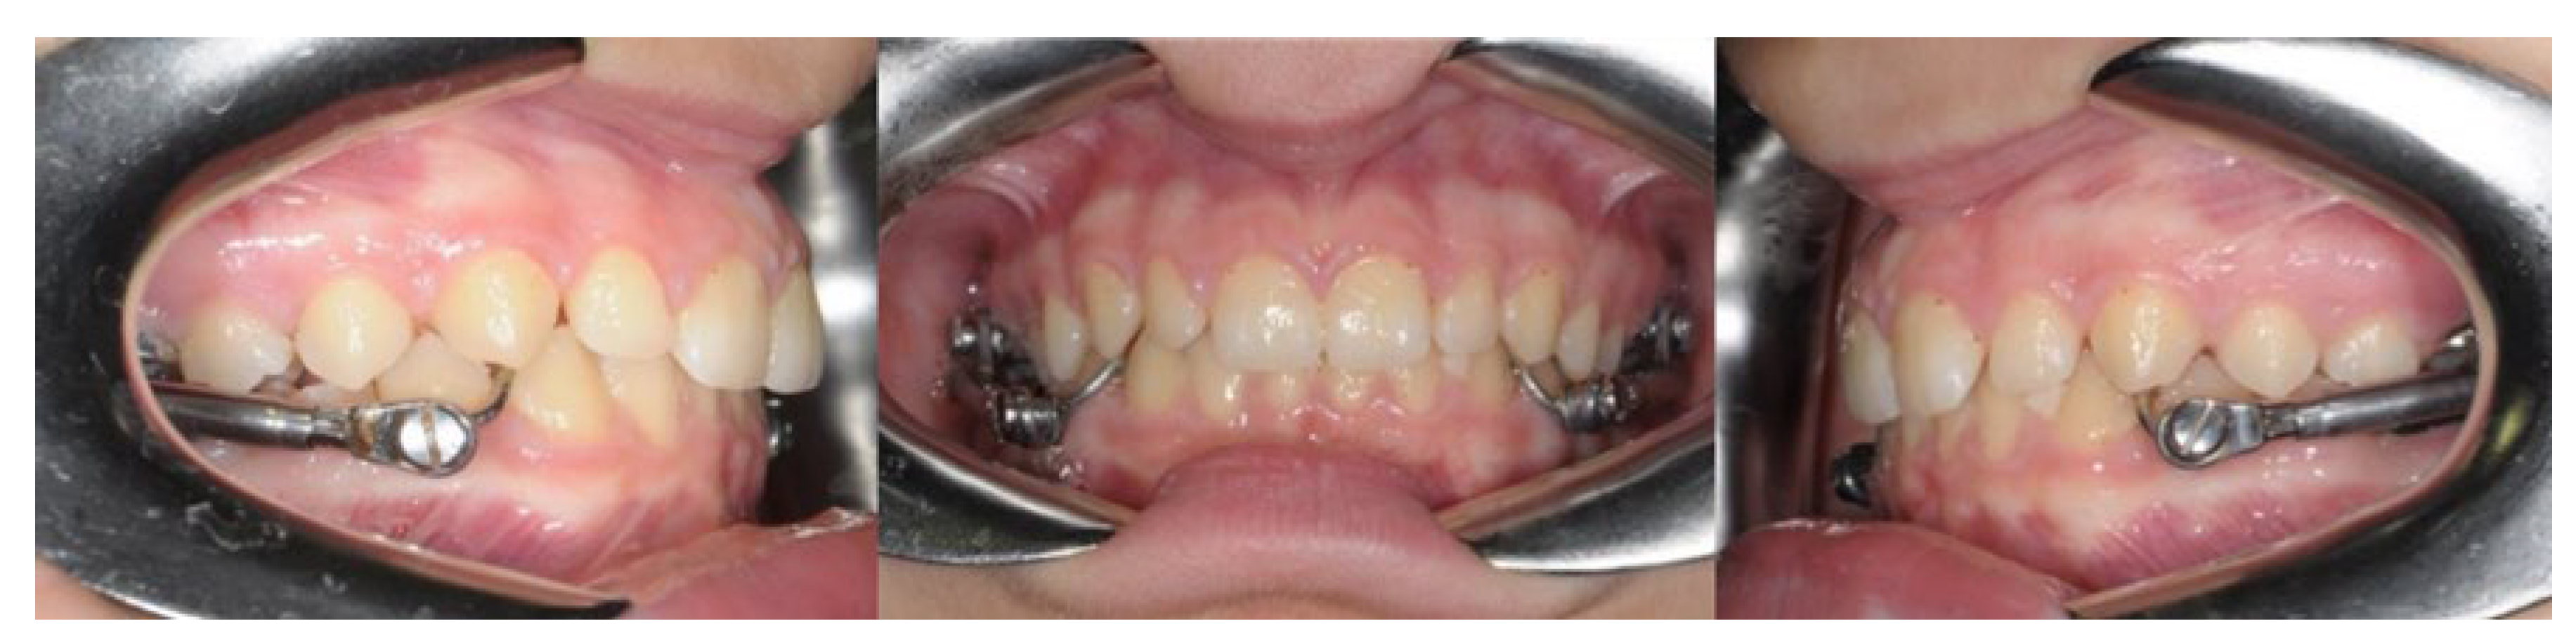

2.1. Group H

2.2. Group EA

2.3. Group C